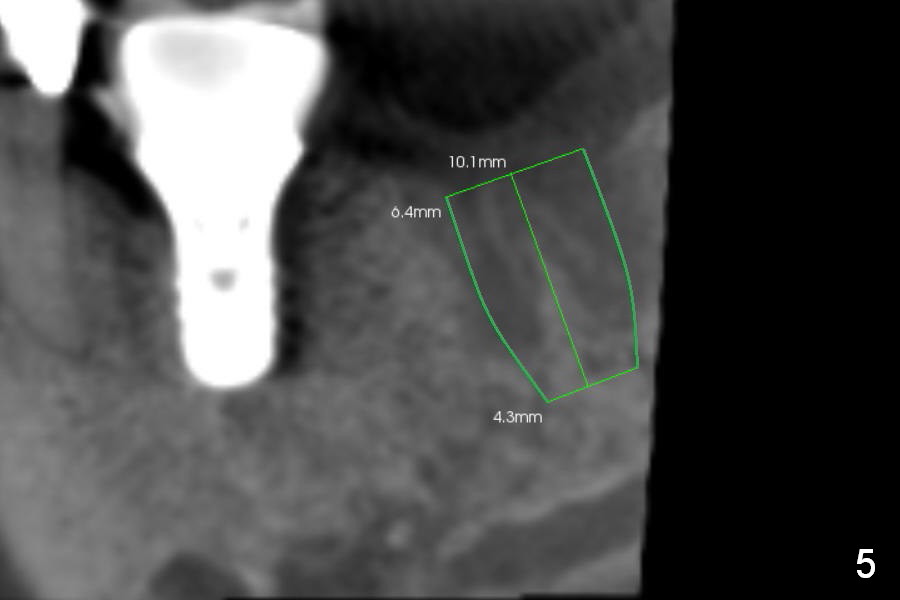

Preop CBCT shows that a 6.4x10 mm implant is appropriate if placed in the middle of the socket (septum), 6 mm from the crown of #30 (Fig.5). Coronal section confirms that because of the lingual slope of the socket, osteotomy should be placed lingually (Fig.6 red line). Three-D image is shown in Fig.7.